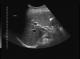

Post cholecystektomi patient. Normalvid gallgång i leverhilus (8a)...ändå choledochuskonkrement. Konkrement mellan kryssen. ERCP bekräftar.